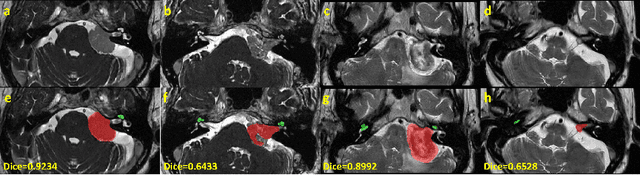

Abstract:Domain Adaptation (DA) has recently raised strong interests in the medical imaging community. While a large variety of DA techniques has been proposed for image segmentation, most of these techniques have been validated either on private datasets or on small publicly available datasets. Moreover, these datasets mostly addressed single-class problems. To tackle these limitations, the Cross-Modality Domain Adaptation (crossMoDA) challenge was organised in conjunction with the 24th International Conference on Medical Image Computing and Computer Assisted Intervention (MICCAI 2021). CrossMoDA is the first large and multi-class benchmark for unsupervised cross-modality DA. The challenge's goal is to segment two key brain structures involved in the follow-up and treatment planning of vestibular schwannoma (VS): the VS and the cochleas. Currently, the diagnosis and surveillance in patients with VS are performed using contrast-enhanced T1 (ceT1) MRI. However, there is growing interest in using non-contrast sequences such as high-resolution T2 (hrT2) MRI. Therefore, we created an unsupervised cross-modality segmentation benchmark. The training set provides annotated ceT1 (N=105) and unpaired non-annotated hrT2 (N=105). The aim was to automatically perform unilateral VS and bilateral cochlea segmentation on hrT2 as provided in the testing set (N=137). A total of 16 teams submitted their algorithm for the evaluation phase. The level of performance reached by the top-performing teams is strikingly high (best median Dice - VS:88.4%; Cochleas:85.7%) and close to full supervision (median Dice - VS:92.5%; Cochleas:87.7%). All top-performing methods made use of an image-to-image translation approach to transform the source-domain images into pseudo-target-domain images. A segmentation network was then trained using these generated images and the manual annotations provided for the source image.

Abstract:Automatic segmentation of vestibular schwannoma (VS) and the cochlea from magnetic resonance imaging (MRI) can facilitate VS treatment planning. Unsupervised segmentation methods have shown promising results without requiring the time-consuming and laborious manual labeling process. In this paper, we present an approach for VS and cochlea segmentation in an unsupervised domain adaptation setting. Specifically, we first develop a cross-site cross-modality unpaired image translation strategy to enrich the diversity of the synthesized data. Then, we devise a rule-based offline augmentation technique to further minimize the domain gap. Lastly, we adopt a self-configuring segmentation framework empowered by self-training to obtain the final results. On the CrossMoDA 2022 validation leaderboard, our method has achieved competitive VS and cochlea segmentation performance with mean dice scores of 0.8178 $\pm$ 0.0803 and 0.8433 $\pm$ 0.0293, respectively.

Abstract:Automatic methods to segment the vestibular schwannoma (VS) tumors and the cochlea from magnetic resonance imaging (MRI) are critical to VS treatment planning. Although supervised methods have achieved satisfactory performance in VS segmentation, they require full annotations by experts, which is laborious and time-consuming. In this work, we aim to tackle the VS and cochlea segmentation problem in an unsupervised domain adaptation setting. Our proposed method leverages both the image-level domain alignment to minimize the domain divergence and semi-supervised training to further boost the performance. Furthermore, we propose to fuse the labels predicted from multiple models via noisy label correction. In the MICCAI 2021 crossMoDA challenge, our results on the final evaluation leaderboard showed that our proposed method has achieved promising segmentation performance with mean dice score of 79.9% and 82.5% and ASSD of 1.29 mm and 0.18 mm for VS tumor and cochlea, respectively. The cochlea ASSD achieved by our method has outperformed all other competing methods as well as the supervised nnU-Net.

Abstract:Automatic methods to segment the vestibular schwannoma (VS) tumors and the cochlea from magnetic resonance imaging (MRI) are critical to VS treatment planning. Although supervised methods have achieved satisfactory performance in VS segmentation, they require full annotations by experts, which is laborious and time-consuming. In this work, we aim to tackle the VS and cochlea segmentation problem in an unsupervised domain adaptation setting. Our proposed method leverages both the image-level domain alignment to minimize the domain divergence and semi-supervised training to further boost the performance. Furthermore, we propose to fuse the labels predicted from multiple models via noisy label correction. Our results on the challenge validation leaderboard showed that our unsupervised method has achieved promising VS and cochlea segmentation performance with mean dice score of 0.8261 $\pm$ 0.0416; The mean dice value for the tumor is 0.8302 $\pm$ 0.0772. This is comparable to the weakly-supervised based method.